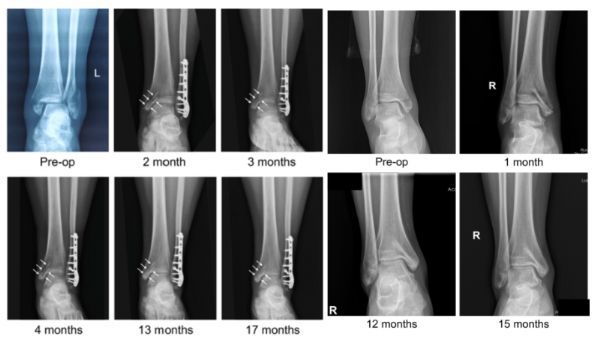

近日,国际骨科临床转化期刊《Journal of Orthopaedic Translation》在线发表了由上海交大戴尅戎院士、郝永强教授团队和丁文江院士、袁广银教授团队合作发表的可降解镁合金骨钉1-2年的临床试验观察结果,所有患者术后内踝骨折愈合,功能恢复。研究证实了可降解镁合金螺钉治疗内踝骨折的临床疗效及其生物安全性,为全降解镁合金植入物等高端医疗器械进一步的临床推广应用奠定了坚实基础,相关成果以“Effectiveness and safety of biodegradable Mg-Nd-Zn-Zr alloy screws for the treatment of medial malleolar fractures”为题在线发表于Journal of Orthopaedic Translation,27 (2021) 96–100。这是国内首个可降解医用镁合金临床试验的公开报道,也是国际首款含有功能涂层的可降解镁合金骨钉的临床试验结果的公开报道,具有里程碑意义。